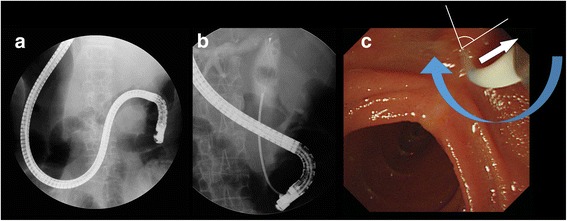

A 74-year-old woman presented with epigastric pain and jaundice for 3 days. She had epigastric tenderness but a negative Murphy’s sign. The aspartate transaminase level was elevated to 191 IU/L, the alanine transaminase level to 79 IU/L, and total bilirubin level to 15.23 mg/dL. The alkaline phosphatase level was 409 IU/L and γ-glutamyltransferase level was 815 IU/L. Computed tomography (CT) revealed diffuse dilatation of biliary tree, with multiple intrahepatic duct stones and common bile duct (CBD) stones (Fig. 1a). Previously undiagnosed situs inversus viscerum was also found on CT (Fig. 1b). Before performing ERCP, an endoscopic examination using conventional gastroscopy was performed, which showed a reversed anatomy of the gastrointestinal tract. For removal of bile duct stones, the patient was placed in the prone position and the endoscopists performed ERCP from the right side of the table. The endoscope was rotated 180° counterclockwise in the stomach. After entering the duodenum, the endoscope was again shortened using a 180° counterclockwise rotation (Fig. 2a,b, Additional file 1 and Additional file 2). Although access was relatively easy, the ampulla in the endoscopic view was deviated to right side and right-upward direction (Fig. 2c). Moreover, it was difficult to control the endoscope owing to the looped endoscope shaft. In the first ERCP, the cholangiogram revealed a large filling defect and diffuse dilatation of tge CBD. After performing a sphinterotomy and mechanical lithotripsy, we removed a bile duct stone. However, several stones still remained in the CBD on follow-up cholangiography.